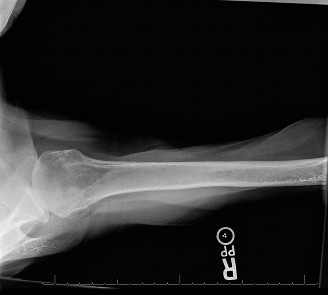

Thorough preoperative imaging and templating are mandatory. Standard radiographic evaluation includes a true anteroposterior (Grashey) view, an axillary lateral view, and a scapular Y view. These assess joint space narrowing, inferior humeral osteophytes (goat's beard), and gross glenoid morphology.

A non-contrast Computed Tomography (CT) scan of the shoulder is critical for evaluating glenoid version, inclination, and available bone stock. The modified Walch classification is utilized to categorize glenoid morphology based on axial CT imaging:

* Type A: Centered humeral head with concentric wear (A1: minor erosion, A2: major central erosion).

* Type B: Posterior subluxation of the humeral head with asymmetric posterior wear (B1: narrowing, no biconcavity; B2: biconcave glenoid with posterior erosion; B3: monoconcave posterior wear with >15 degrees retroversion).

* Type C: Dysplastic glenoid with >25 degrees of retroversion.

* Type D: Anterior subluxation with anterior glenoid erosion.